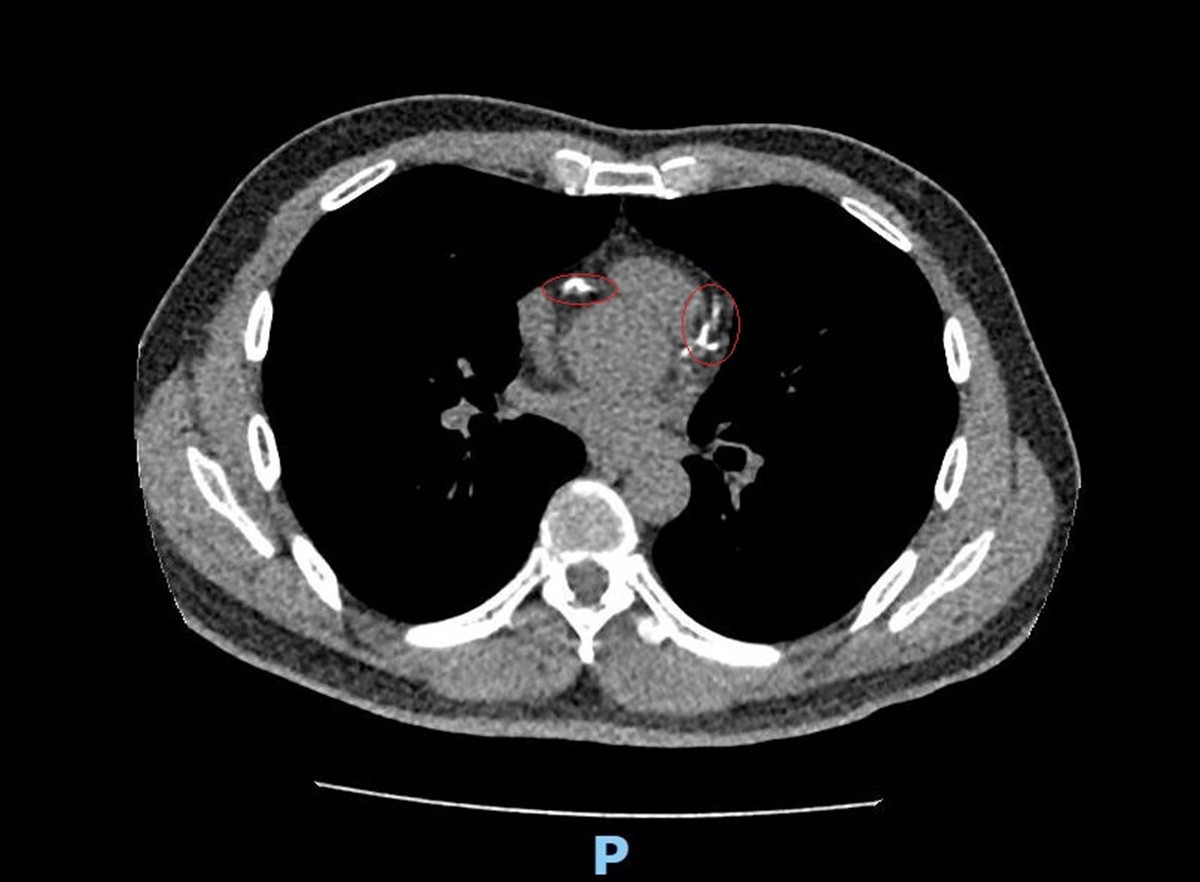

李學林表示,林先生日前接受肺癌篩檢時意外發現心血管鈣化,但無法確認是血管內或血管外鈣化。因患者平時已出現胸悶症狀,進一步做心臟冠狀動脈電腦斷層,確認為3條主要冠狀動脈血管內鈣化狹窄達85%以上,若未及時處理,隨時可能引發急性心肌梗塞。

李學林說,醫療團隊透過心導管手術搭配IVL技術,利用震波氣球貼近血管壁發出超聲壓力波,擊碎血管壁的堅硬鈣化斑塊,讓原本僵硬的血管恢復擴張性,為支架放置創造理想的環境,再植入3支支架,使支架能完整展開、貼合血管,降低支架血栓及再狹窄的風險。